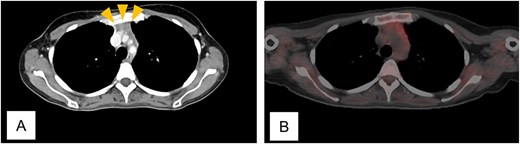

Twelve months after completion of chemotherapy, follow-up CT revealed an anterior mediastinal mass and enlargement of a left axillary lymph node (Fig. 2A). A biopsy of the axillary node showed no malignant cells. Fluorodeoxyglucose positron emission tomography/CT (FDG-PET/CT) demonstrated no abnormal uptake (Fig. 2B). A diagnosis of thymic hyperplasia was made.

Computed tomogram and fluorodeoxyglucose positron emission tomogram/computed tomogram of Case 1. (A) Chest contrast-enhanced computed tomogram shows a 2 x 1 cm anterior mediastinal mass with increased fat attenuation (arrowhead). (B) No abnormal uptake is seen in the thymic mass on fluorodeoxyglucose positron emission tomogram/computed tomogram.